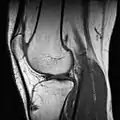

| Magnetic resonance imaging (MRI) alias Nuclear magnetic resonance (NMR) | high strength (0.15 to 1.5 teslas)[4] are used to excite protons that produce the record results (like CT scan). It can show particular tissues more clearly than CT.;[4] video link |

A 3 tesla MRI scanner